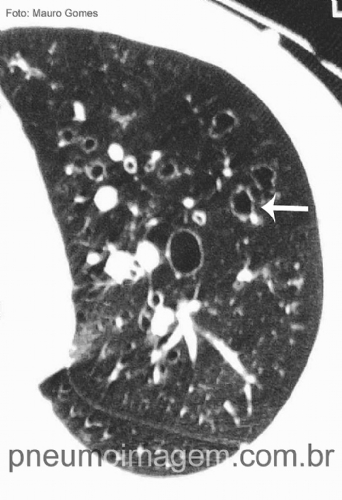

Em longo prazo foram observados menos plugues mucosos à TCAR no grupo manitol, adesão alta, bem tolerado e os efeitos adversos foram semelhantes ao placebo.

Veja imagens de bronquiectasias não fibrocísticas no PneumoImagem

clicando aqui.